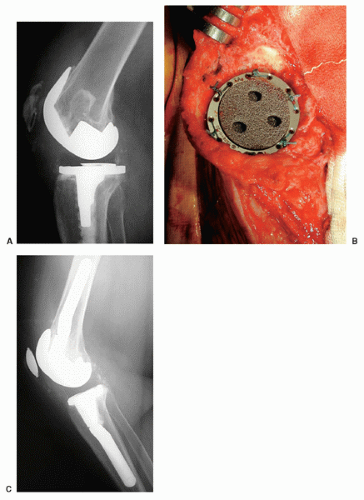

중요한 것은 Type II 인데, 폄근의 기능을 상실하였기 때문에 수술적인 치료가 필요합니다. 안에 들어간 implant는 정상일 수도 있으며, Bone Stock 이 남아있는 정도를 확인하여 수술의 종류를 설정할 수 있습니다. (대게 고령에 뼈 상태가 좋을 수 없으니 Partial patellectomy를 가장 많이 할 것 같습니다.)

아래와 같은 방식으로 여러가지 수술을 시행해 볼 수 있습니다. (ORIF, 뼈와 근육을 연결한 부위를 채취하여 기존의 patella 부분과 tibia 부분을 연결하도록 꼬매서 폄근육을 재건하는 경우, Suture anchor를 이용해서 repair 하는 경우, K-wire를 이용한 tension band wiring을 시행해 볼 수 있습니다.)

심하게 골절이 있는 경우는 슬개골을 재거하는 것 까지 생각해야 합니다.